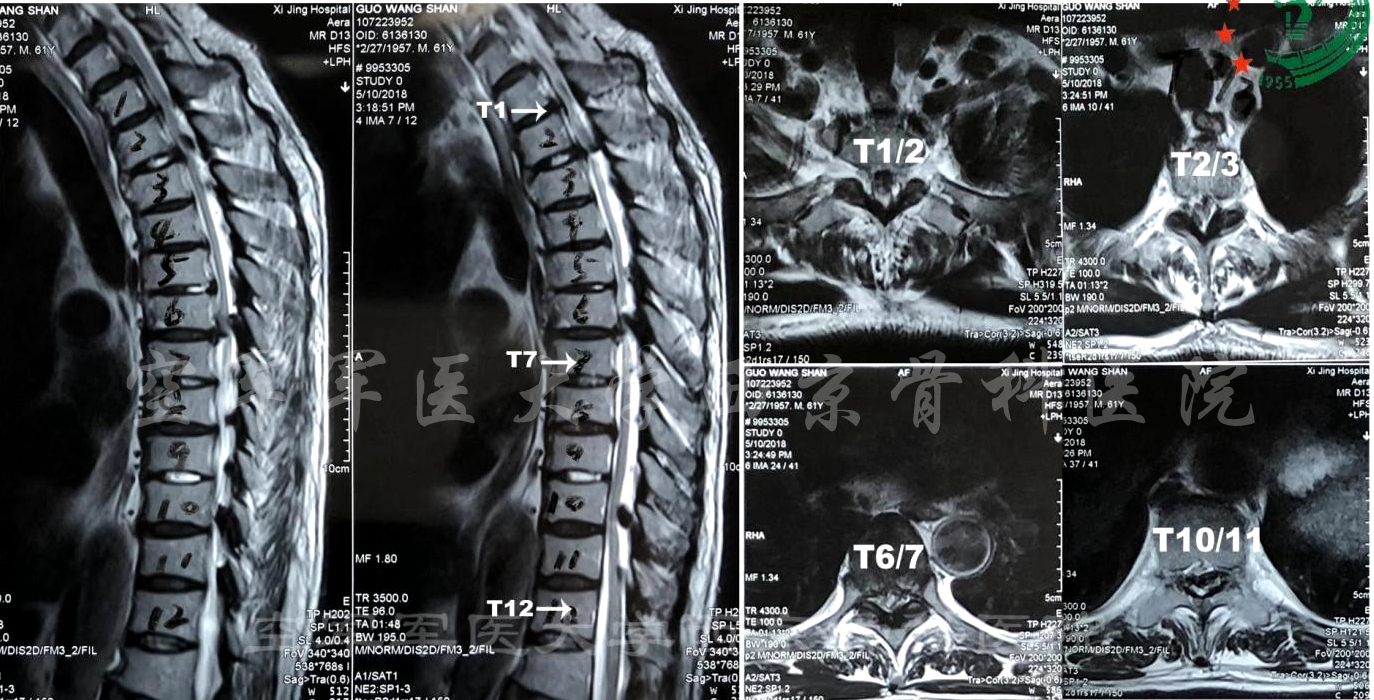

术前CT